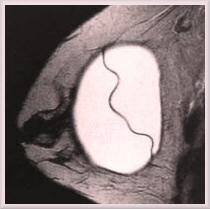

A MR scan of a round, smooth

walled, silicone gel implant in

place within a breast